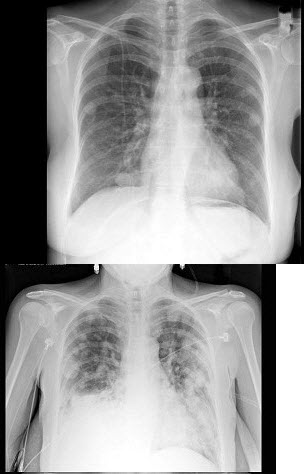

女,51岁,胸闷、咳嗽、咳痰2月余,3年前被确诊为子宫平滑肌肉瘤,结合胸片,最可能的诊断是()

A.粟粒型肺结核

B.肺转移瘤

C.结节病

D.胶原病

E.真菌病